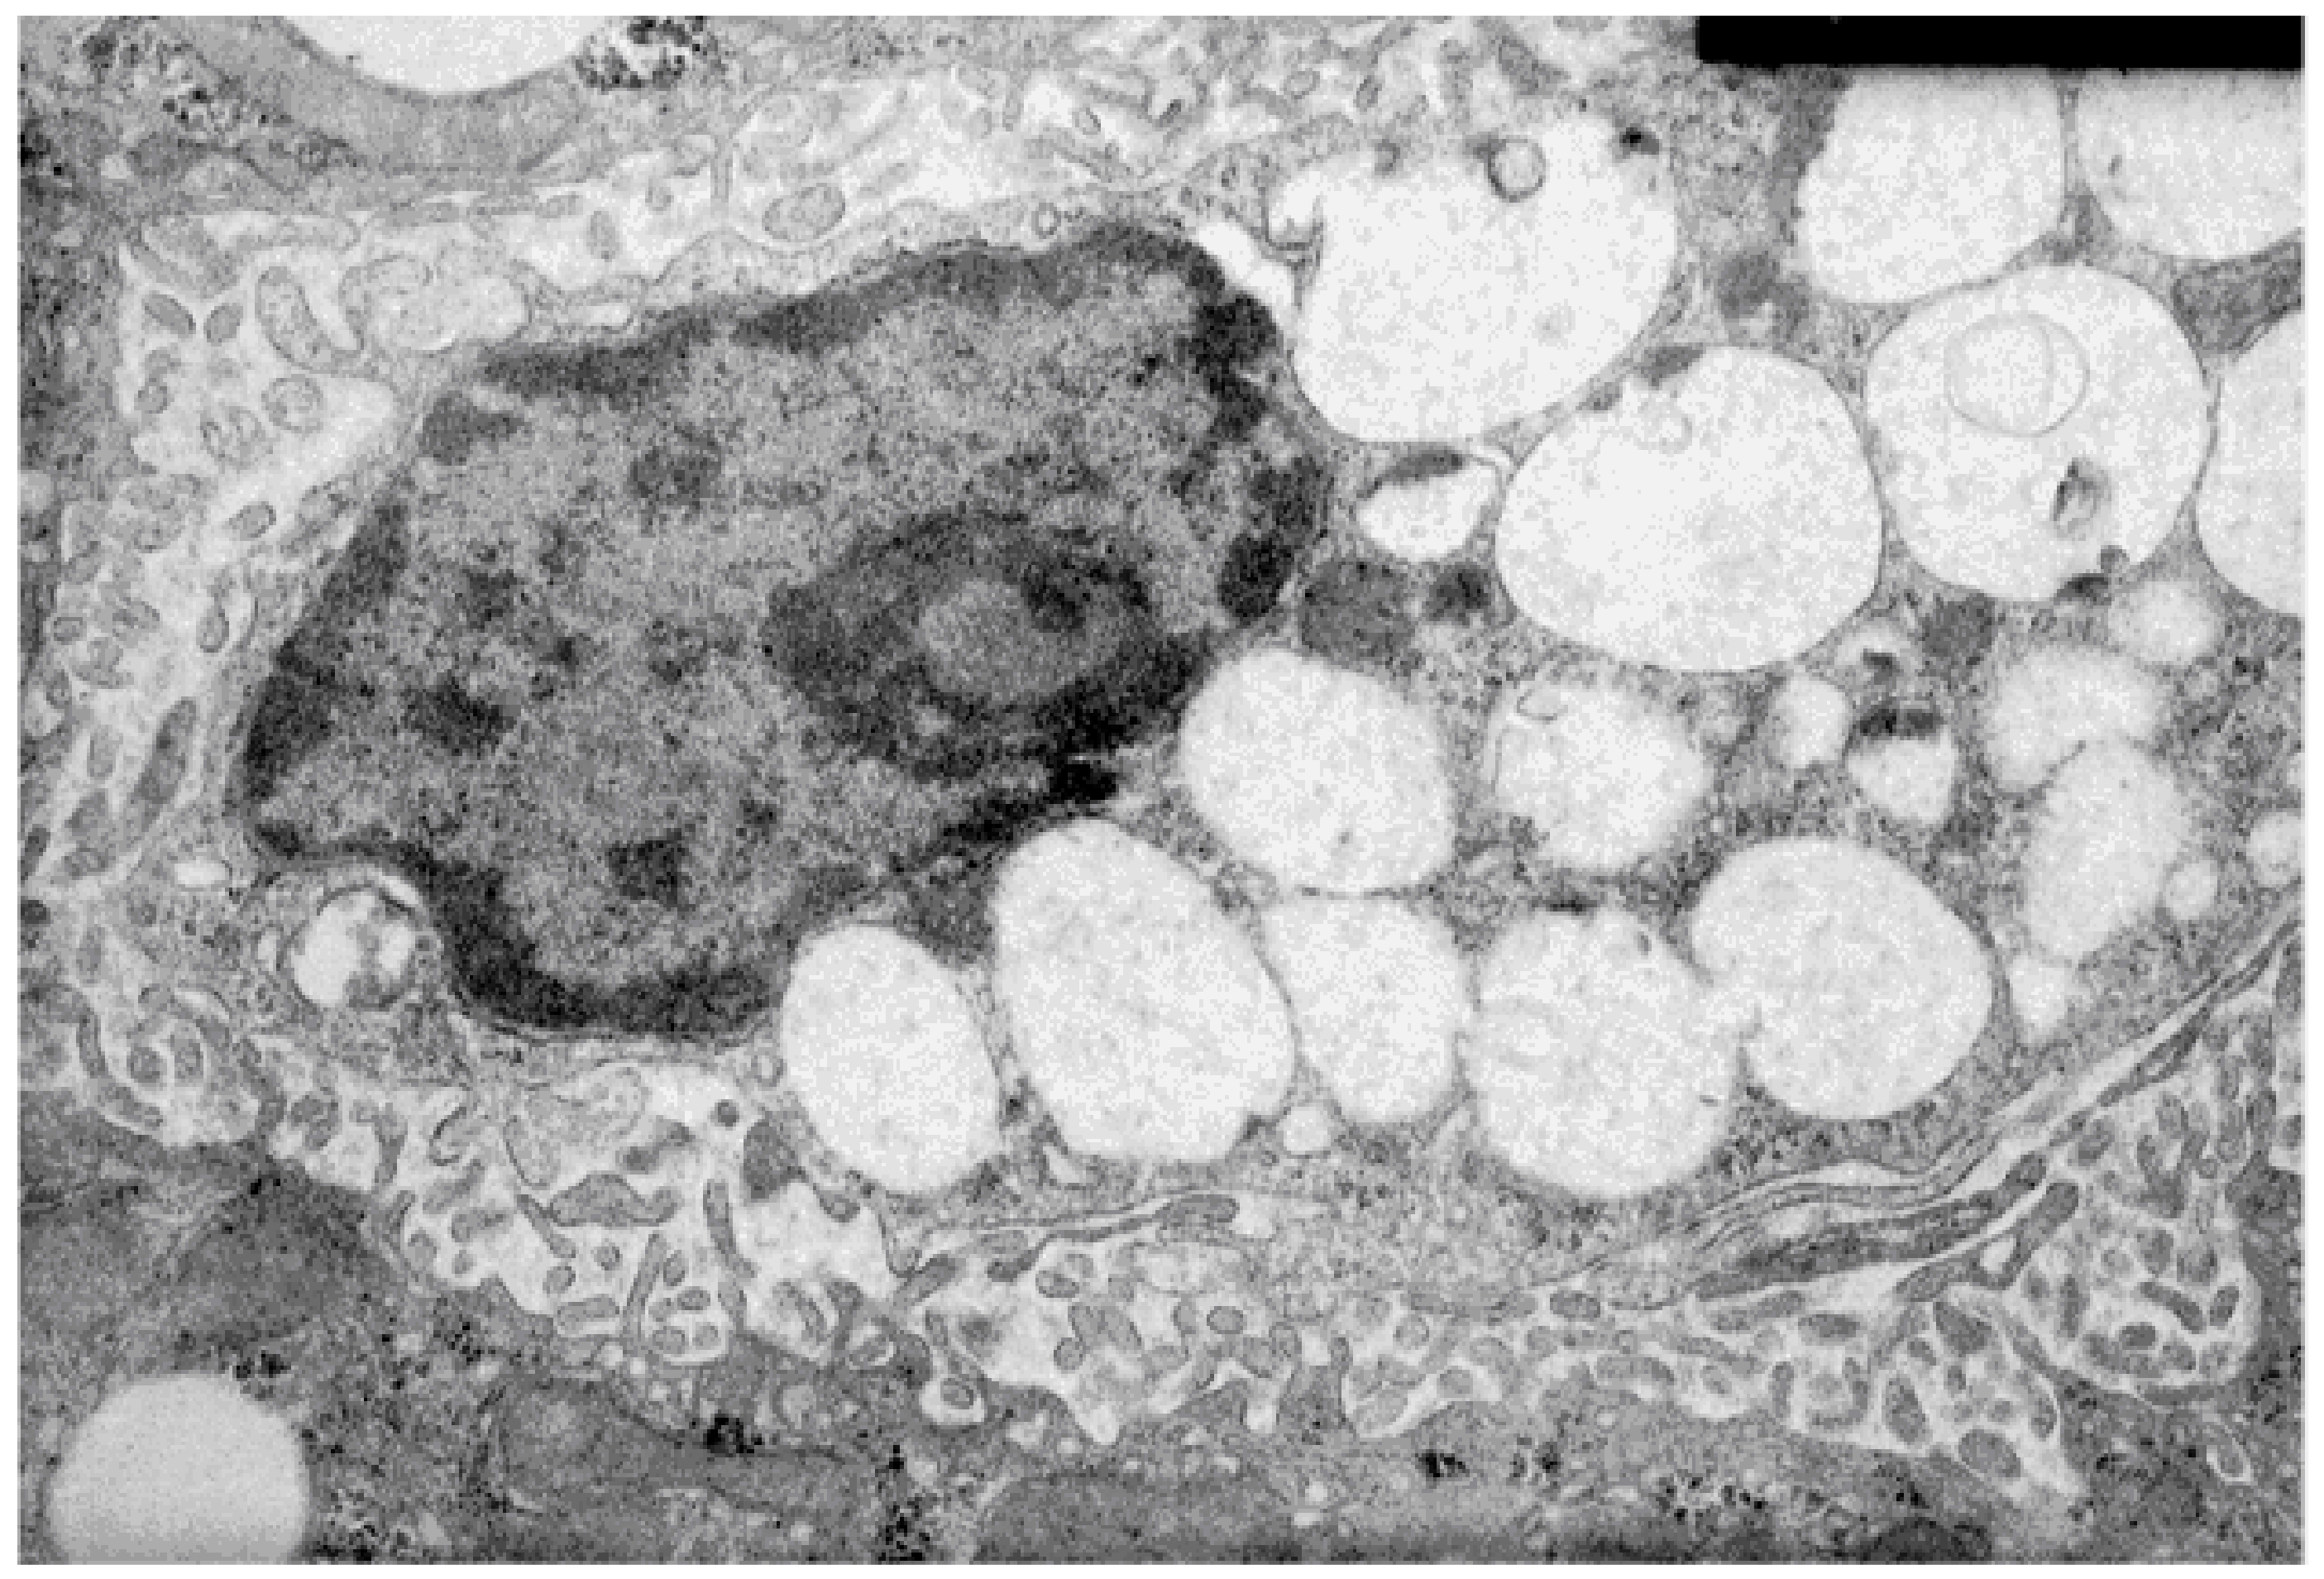

- Shiozaki, M.; Hayakawa, N.; Shibata, M.; Koike, M.; Uchiyama, Y.; Gotow, T. Closer association of mitochondria with lipid droplets in hepatocytes and activation of Kupffer cells in resveratrol-treated senescence-accelerated mice. Histochem. Cell Biol. 2011, 136, 475–489. [Google Scholar] [CrossRef] [PubMed]